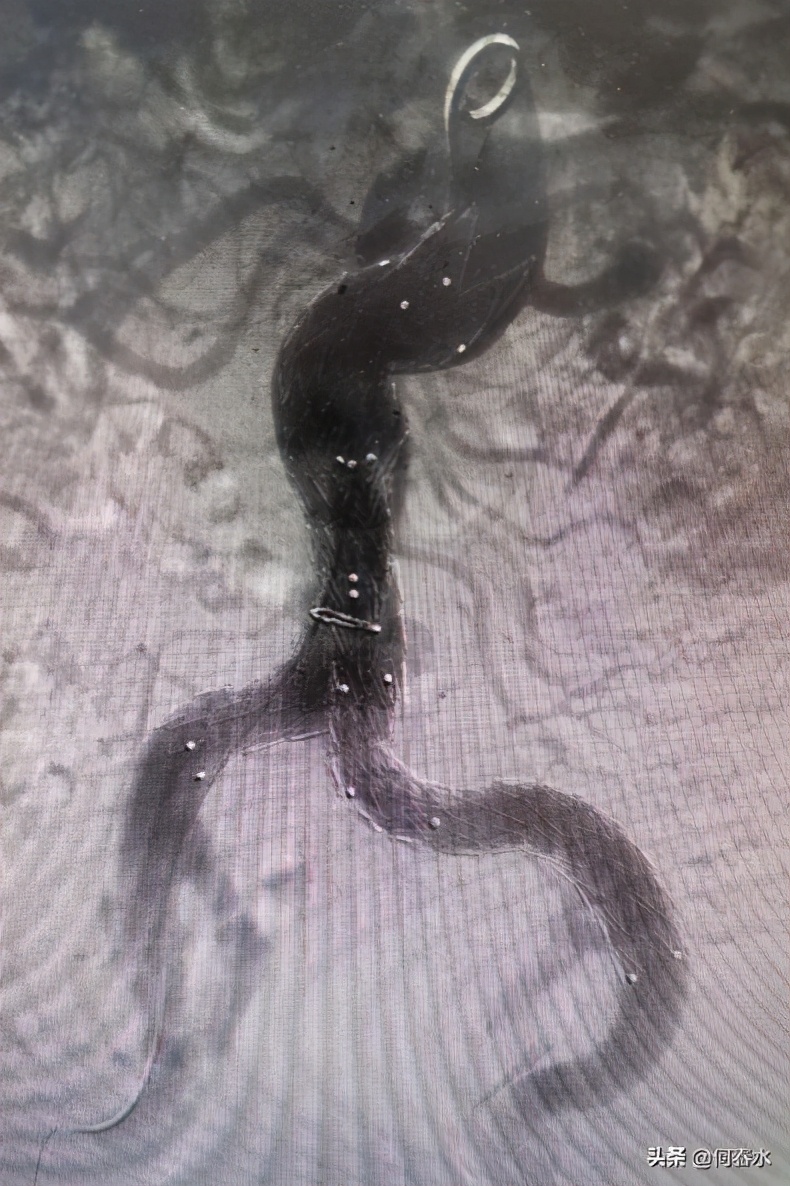

经过近2个小时紧锣密鼓的奋战,在局麻下,双侧腹股沟仅行两处2cm切口,顺利完成了腹主动脉+双髂动脉覆膜支架腔内隔绝手术。术后,患者腹部疼痛得到了缓解。

术后第5天,我院血管外科医生对患者进行床旁超声复查,支架位置在位良好,动脉瘤被支架隔绝,未见内漏。